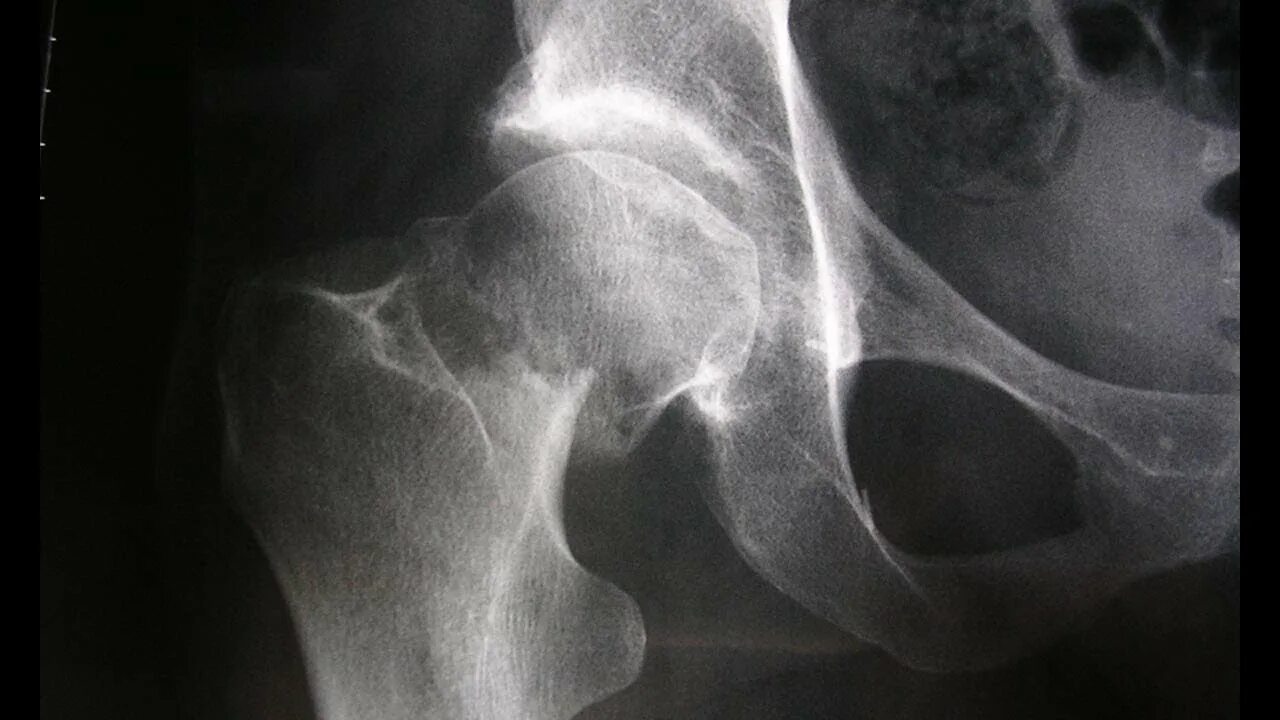

Source x rays